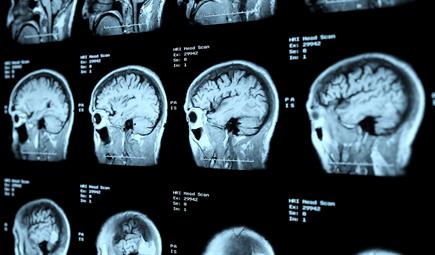

السكتة الدماغية هي حالة طبية طارئة تصيب الشخص عندما يتوقّف تدفق الدم إلى الدماغ أو عند انخفاض كميّة الدم المتدفّقة إلى الدماغ. ومن الضروري معلاجة هذه الحالة في شكل فوري للحدّ من الإصابة بتلف في الدماغ ومنع حدوث المزيد من المضاعفات.

وثمة نوعان من السكتة الدماغية؛ الإقفارية والنزفية.

تنجم السكتة الدماغية الإقفارية عن جلطة دموية تتسبّب بتوقف تدفّق الدم في الشرايين التي تغذي الدماغ. فالأنسجة الدماغية التي لا تحصل على كمية كافية من الأكسجين تفقد القدرة على الصمود وتبدأ بالموت، ما يُسفر عن أعراض يُمكن رصدها. وغالباً ما تحدث التجلطات الدموية نتيجة تصلّب في الشرايين، وهو عبارة عن تكدّس لتراكمات دهنية في الشرايين. وقد تتكدّس هذه التراكمات في القلب وتنتقل من القلب لتقبع في أحد الأوعية الدموية في الدماغ.

ويُمكن للسكتة الدماغية النزفية الأقل شيوعاً أن تحدث بسبب تسرّب أو نزيف في الأوعية الدموية في الدماغ، ما يؤدّي إلى تجمّع الدم في مادة الدماغ وإحداث ضرر موضعي فيه.